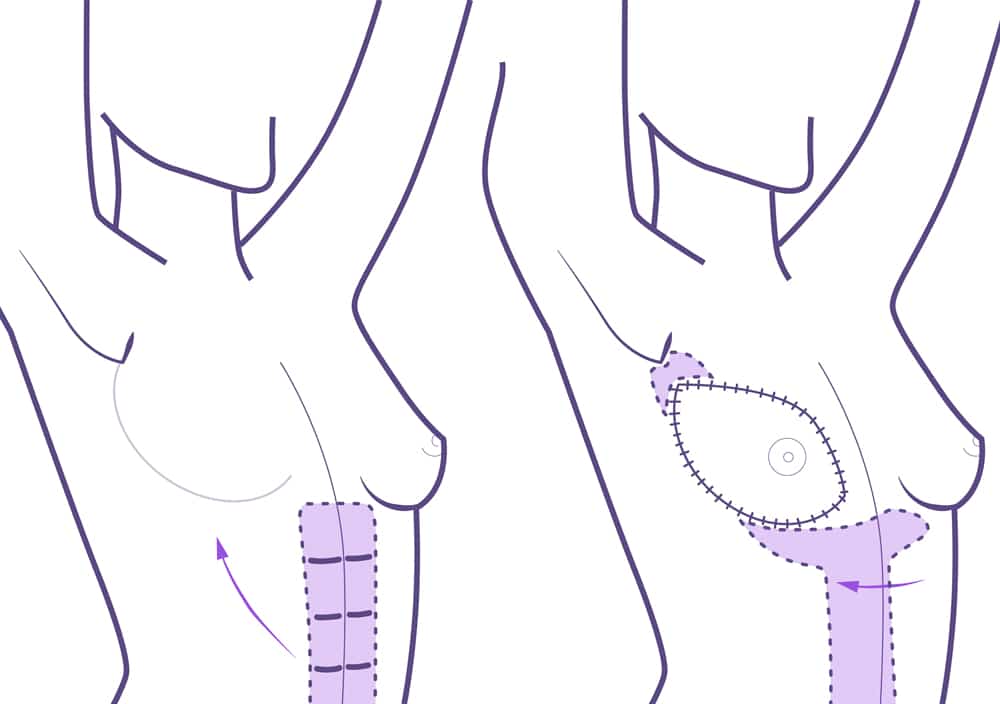

Consiste en la movilización o el trasplante de tejidos de otras zonas del cuerpo como el abdomen, la espalda o las nalgas.

En algunos casos estos tejidos siguen unidos a su sitio original, conservando su vascularización, y son trasladados hacia la mama mediante un túnel que corre por debajo de la piel.

En otros casos son separados completamente de su sitio original y son trasplantados al pecho mediante la conexión a los vasos sanguíneos de esta zona.

Esta técnica es más compleja, deja más cicatriz y el período de recuperación es mayor. Sin embargo, el resultado estético es mucho más natural. Esta operación se realiza bajo anestesia general con una estancia hospitalaria de 3 días.